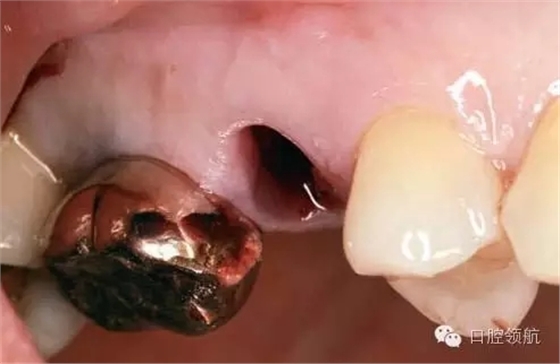

患者10年前,在外院于( 左上第六顆牙)區(qū)行上頜竇底提升術(shù)同期植入種植體,經(jīng)過10年上頜竇內(nèi)生成骨完全吸收消失了(圖1)?;颊叽舜蝸碓菏且驗猷徰? 左上第五顆牙) 不能保存,希望行種植修復(fù)治療。

圖1 術(shù)前牙片。由于上頜竇底黏膜提升植骨術(shù)而在上頜竇內(nèi)生成的骨已完全消失。

術(shù)前口內(nèi)未見種植體周圍有炎癥等異常表現(xiàn)(圖2),翻開黏骨膜瓣后,10年前手術(shù)入路的痕跡在頰側(cè)骨面已經(jīng)觀察不到了(圖3)。

圖2 ( 左上第五顆牙)拔除后即刻的口內(nèi)像。